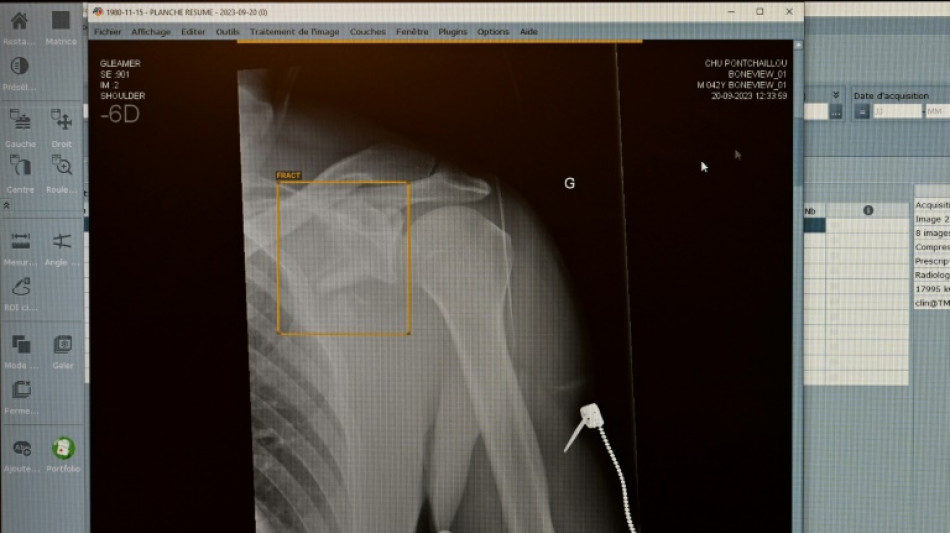

Zweitmeinung von KI bei Gesundheitsproblemen: Für jeden Zweiten vorstellbar / Foto: Damien MEYER - AFP/Archiv

Jeder Zweite kann sich vorstellen, eine Anwendung mit Künstlicher Intelligenz (KI) bei Gesundheitsproblemen um eine Zweitmeinung zu ersuchen. Nach einer am Dienstag in Berlin veröffentlichten Umfrage des Digitalverbandes Bitkom ist das für 51 Prozent der Teilnehmenden eine Option.

Fast die Hälfte der Befragten (47 Prozent) traut einer KI laut Befragung in bestimmten Fällen sogar bessere Diagnosen zu als Menschen. Auf der Suche nach Informationen zu Diagnosen, Nebenwirkungen verordneter Arzneimittel oder zur Abklärung von Symptomen haben sich demnach sechs Prozent schon einmal bei einer KI bedient - etwa über Symptomchecker-Apps oder Chatbots wie ChatGPT.